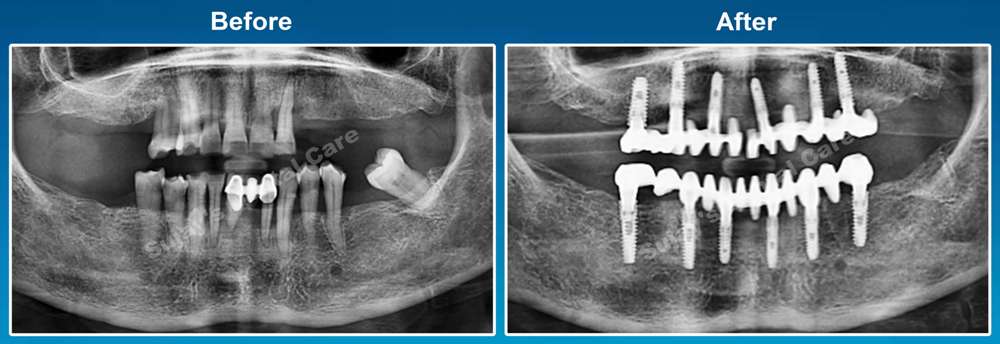

Before & After